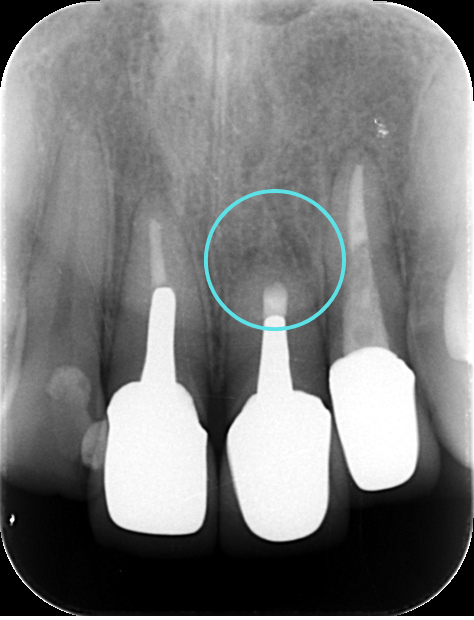

術後すぐ

術後3ヶ月のレントゲン写真

術後1年のレントゲン写真

根尖病変によって骨が溶かされてしまった空間も、歯根端切除術によって感染源が適切に除去され、根管が緊密に封鎖されると、体本来の治癒力によって再び新しい骨(新生骨)が作られていきます。 レントゲンでは、術直後は黒い影(骨がない状態)だった部分が、時間の経過とともに徐々に白く(骨が再生してきた状態)映るようになります。この「新生骨の出現」が、外科的歯内療法の成功を示す客観的な証拠となります。

今回の患者さんも、術後の定期検診にお越しいただきました。 術後6ヶ月の時点でのレントゲン写真では、手術前に黒い影として見えていた根尖病変部、および歯根を切除したスペースに、白く不透明な影、すなわち「新生骨」が順調に再生してきていることが明確に確認されました。